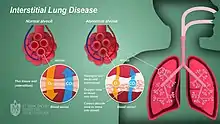

| Interstitial lung disease | |

Interstitial lung disease (ILD), or diffuse parenchymal lung disease (DPLD),[3] is a group of respiratory diseases affecting the interstitium (the tissue) and space around the alveoli (air sacs) of the lungs.[4] It concerns alveolar epithelium, pulmonary capillary endothelium, basement membrane, and perivascular and perilymphatic tissues. It may occur when an injury to the lungs triggers an abnormal healing response. Ordinarily, the body generates just the right amount of tissue to repair damage, but in interstitial lung disease, the repair process is disrupted, and the tissue around the air sacs (alveoli) becomes scarred and thickened. This makes it more difficult for oxygen to pass into the bloodstream. The disease presents itself with the following symptoms: shortness of breath, nonproductive coughing, fatigue, and weight loss, which tend to develop slowly, over several months. The average rate of survival for someone with this disease is between three and five years.[5] The term ILD is used to distinguish these diseases from obstructive airways diseases.